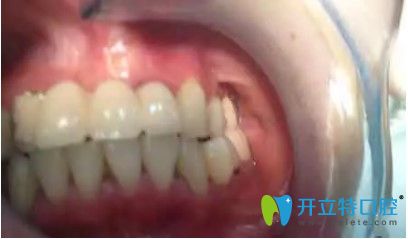

刘女士,33岁,据她描述,自己多年前在国内一家口腔医院做了烤瓷冠,但由于时间长变的松动,考虑到自己还年轻,为了一步到位,她来韩国安特丽做了多颗牙种植。

在拆除烤瓷桥后,发现她的口内埋伏牙,把埋伏牙拔除后,很顺利的植入了种植体,完成了种植牙。

刘女士反馈,自己很后悔当初做了烤瓷牙,她表示,自己对韩国的种植牙技术很认可,所以来韩国做了种牙手术。